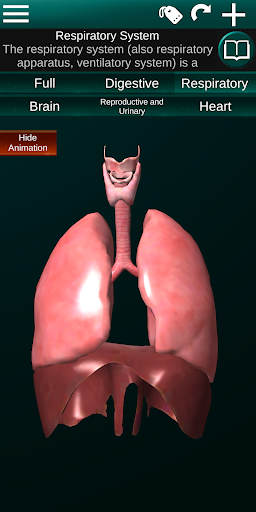

Shows a 3D anatomical model of the main organs of the human body and a description of each one.

* Respiratory system, which includes the trachea, bronchi, lungs and an animation of this system.